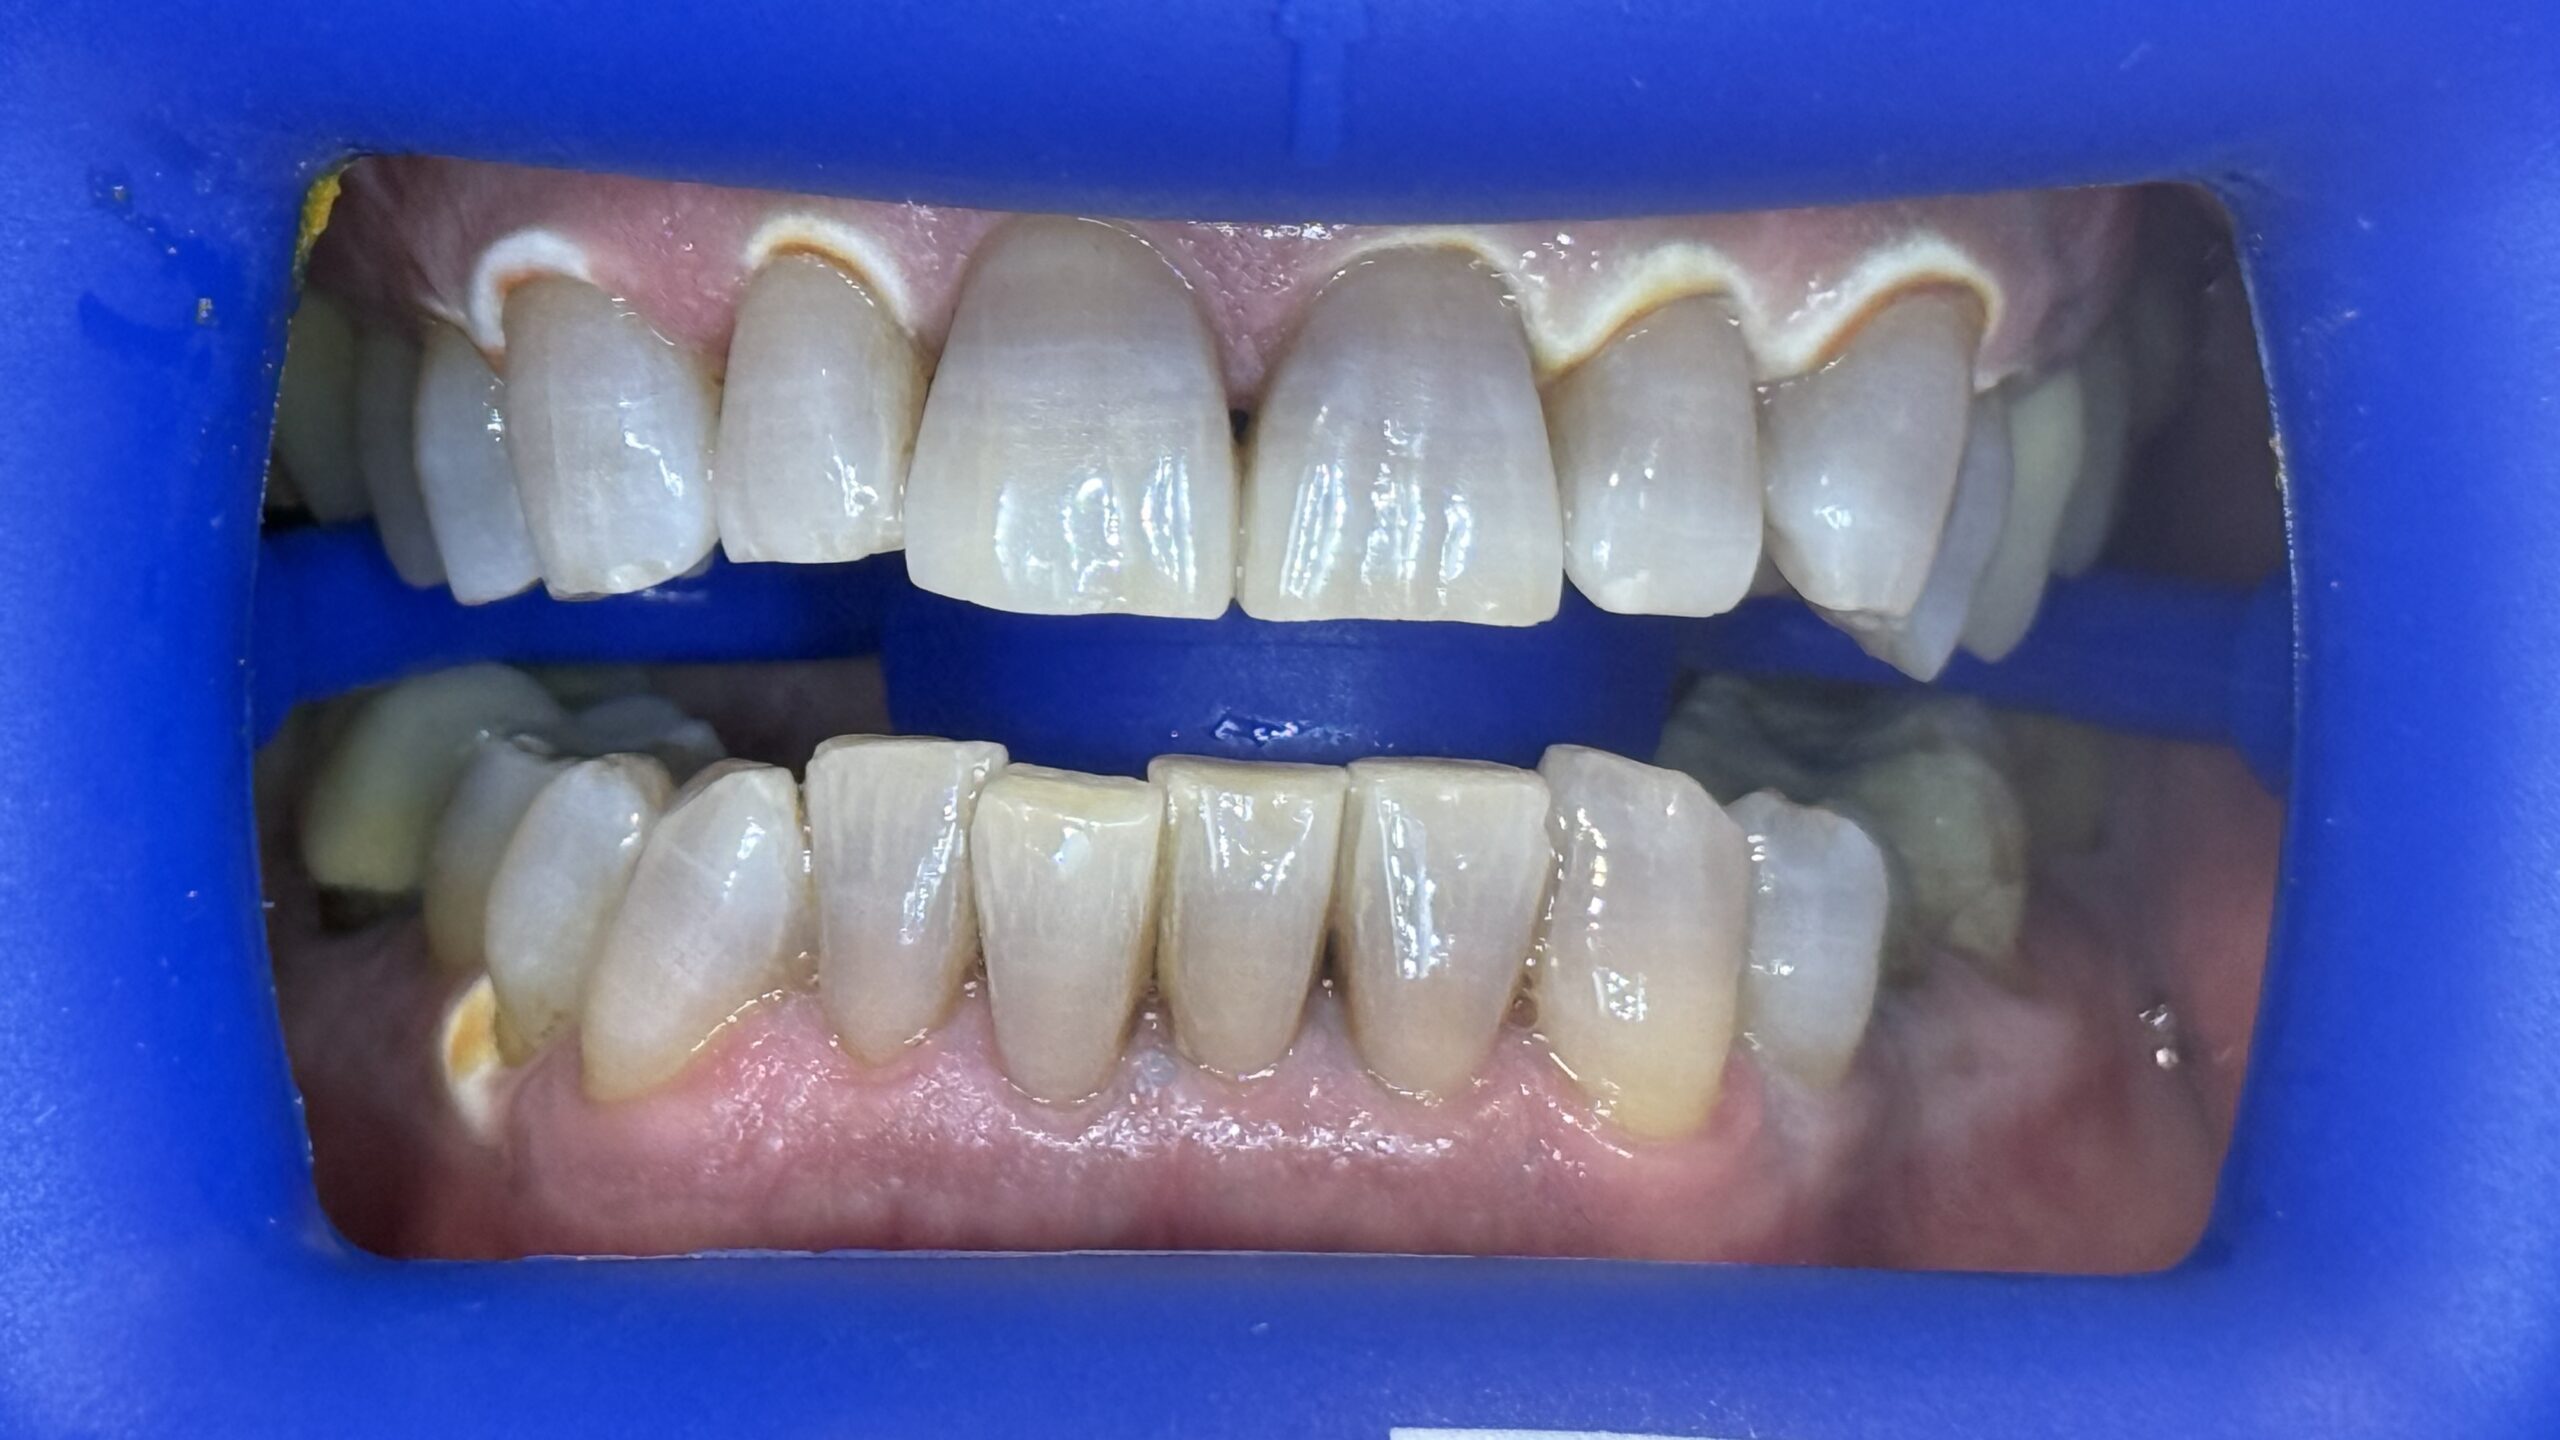

Estetica Dentale

Faccette estetiche in ceramica e corone che si adattano perfettamente al colore e alla forma dei propri denti.eUtilizzo di tecnologie più avanzate